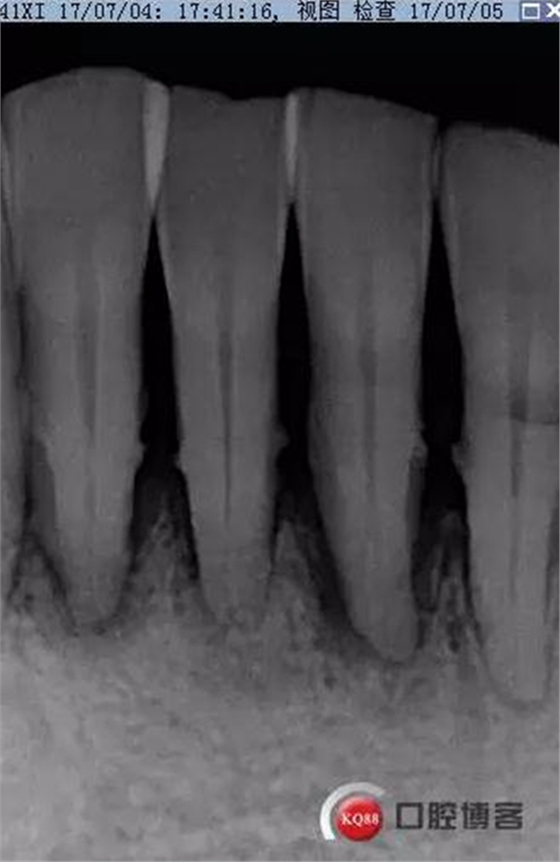

X线示牙槽骨吸收,下颌前牙区可见龈下牙石影像,牙槽骨吸收至根尖1/3,根周透射影像。

X线示根周透射影骨密度增高。

事后再次查看术前片,可以看到两个根管影像,忽略了。